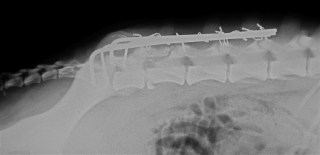

Για τα κατάγματα των σπονδύλων δεν ελήφθη ιδιαίτερη μέριμνα. Η οσφυϊκή μοίρα της σπονδυλικής στήλης ακτινογραφήθηκε μετεγχειρητικώς ώστε να επιβεβαιωθεί η ανάταξη του εξαρθρήματος (Εικ. 6).

Εικ. 6: Μετεγχειρητική ακτινογραφία